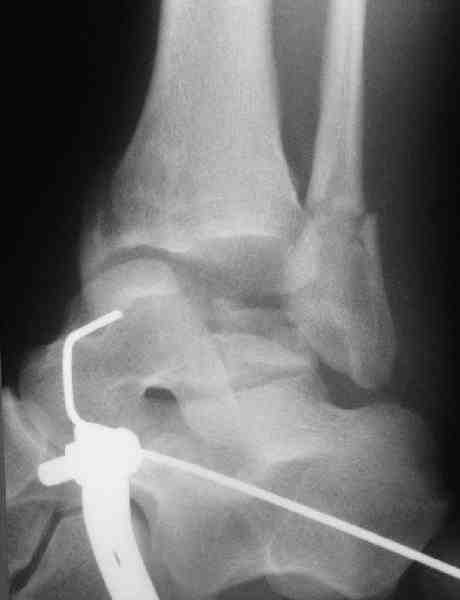

Re: повреждение таранной кости

повторили рентгенограммы и доделали проекции, к единому мнению все еще не пришли